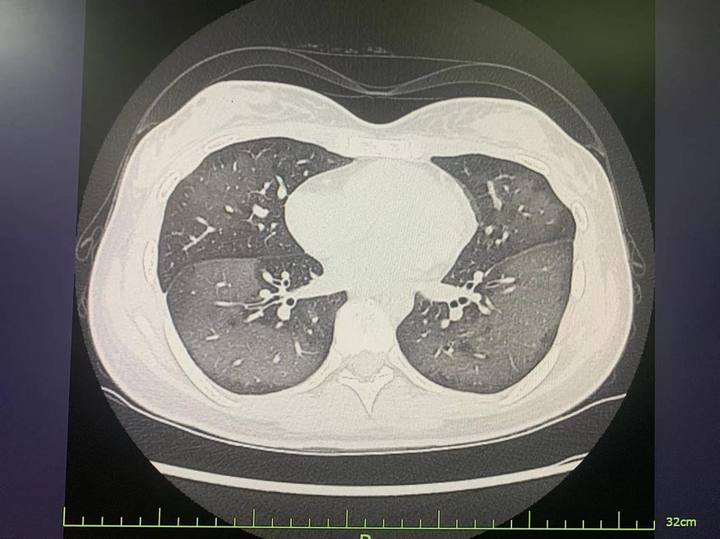

Sau khi nhanh chóng đến bệnh viện, phim chụp CT cho thấy những vùng tổn thương màu trắng lớn ở cả hai phổi và cô được chẩn đoán mắc “viêm phổi hít hóa chất”.

Phim chụp CT cho thấy những vùng tổn thương màu trắng lớn ở cả hai phổi